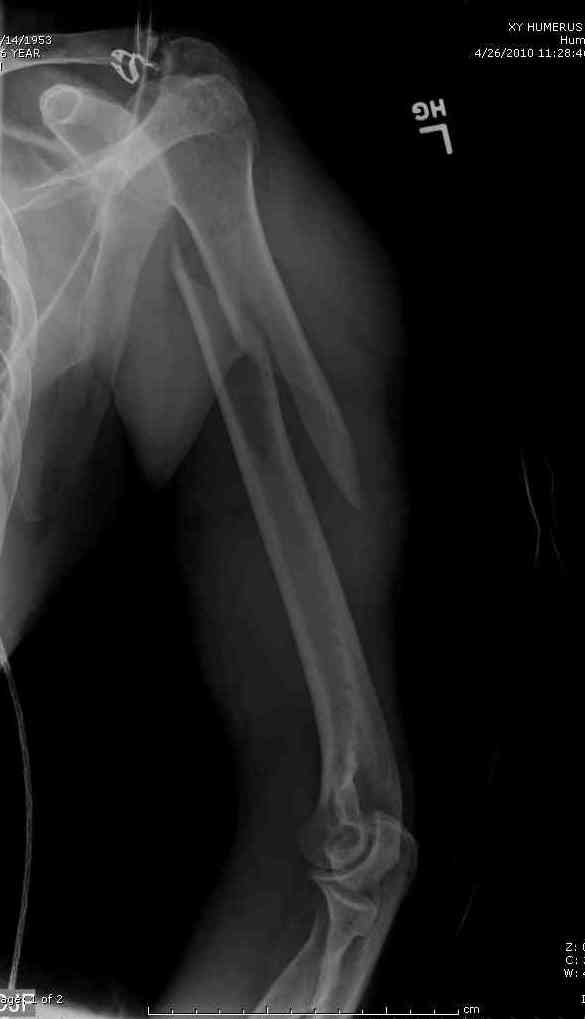

Здесь нет необходимости в серкляже. Вмешиваться на промежуточных отломках приходится, если есть угроза перфорации кожи, или промежуточный отломок попал в фасцию, как пуговица в петлю. В приложении сегментарный оскольчатый перелом плеча в проксимальном отделе, фиксированный больщеберцовым стержнем. Как видите, обошлось без серкляжа. Функция полная.

Пример отличный.

Вот что значит лечить перелом, а не рентгенограмму!

Александр, великолепные снимки! Вопрос - что за гвоздь?

Это укороченный большеберцовый стержень, которые делает предприятие "ЦИТО".

на синтезовский UTN похож))

Скажите пожалуйста, Александр Николаевич, почему Вы использовали большеберцовый гвоздь?

Доступные на тот момент гвозди для плеча имели худшие возможности фиксации в коротком проксимальном отломке.

Уважаемый Александр Николаевич! На продемонстрированных вами рентгенограммах имеется достаточно большое на мой взгляд смещение отломков после фиксации блокируемым гвоздем. На счет полной функции все понятно, а нет ли каких либо сосудистых расстройств конечности? Имею ввиду венозную недостаточность или лимфостаз.